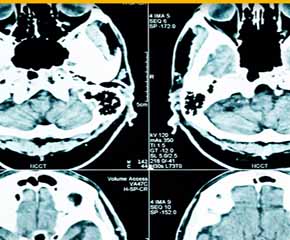

뇌경색 초기증상이 의심된다면 지금 바로 병원을 내방해 진단을 받고 적절한 치료를 손대는 것이 후유증을 감하는데 중요 해요. 시간이 관건이며, 뇌세포의 괴사, 증상 악화, 너무 늦으면 사망에 이를 수 있는 뇌혈관의 괴사를 피하기 위하여 증상이 나타난 뒤에 4시간 이내에 잘 맞은 약물, 시술 또는 수술을 신속히 실시해야 합니다. 치료로 즉시 하셔야 해요.